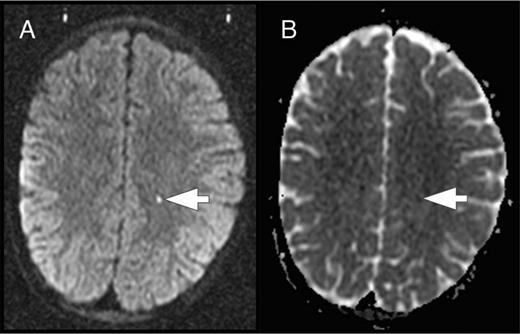

In the course of the SIT trial, some study participants were found to have acute ischemic lesions on screening brain MRIs to determine eligibility for study. These incidentally detected acute ischemic lesions occurred in children who were asymptomatic and clinically well at the time of the MRI. To explore the hypothesis that these acute silent cerebral ischemic events (ASCIEs) were frequent and potentially transient, Quinn et al9 studied the participants of the SIT trial. ASCIE was defined as an area of restricted diffusion on diffusion-weighted imaging (DWI) sequences with a corresponding decrease in signal intensity on the apparent diffusivity coefficient map in the absence of focal neurologic findings that could be explained by the location of the DWI-positive lesion (Figure 5). The temporal information contained in the DWI sequences was used to calculate the incidence of ASCIEs. DWI signal abnormalities occur within 24 hours of the onset of cerebral ischemia and persist for about 10 days, so DWI-positive lesions were considered to be new (incident) and provide 10 patient-days of observation. ASCIEs were detected on 1.3% of MRIs (10 of 771) in 652 children (mean age, 10.0 years), with an incidence of 47.3 events per 100 patient-years (95% CI, 22.7-87.2). In comparison, the incidence of ASCIE was about 40 times higher than the incidence of initial SCI and 4 times higher than recurrent SCI (Table 1). Nine of 10 cases of ASCIEs had no acute medical illnesses in the 2 weeks before MRI. One had just recovered from a recent episode of acute chest syndrome complicated by severe anemia and hypertension and treated with a simple transfusion. Standard neurologic examination was normal for all 10, indicating that the acute cerebral ischemia was clinically covert or silent. Two of 10 children with ASCIEs in this study had follow-up MRIs of the brain, and only 1 had SCI in the same location as the previously detected ASCIE. The main conclusion is that cerebral ischemia occurs far more frequently than previously recognized in SCD. It is important to be aware that ASCIEs often occur during baseline or “steady-state.” Some ASCIEs may be reversible and leave no detectable lesion on MRI, whereas others evolve into typical SCI.

ASCIE. ASCIE is defined as an area of restricted diffusion on DWI sequences (A) with a corresponding decrease in signal intensity on the apparent diffusivity coefficient (ADC) map (B) in the absence of focal neurologic findings that could be explained by the location of the DWI-positive lesion. The lesion has increased signal on T2 and T2-fluid-attenuated inversion recovery images (data not shown).